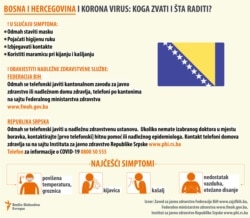

Bosna i Hercegovina nema ministarstvo zdravstva na državnom nivou. Ova oblast je u nadležnostima entiteta (Republika Srpska i Federacija BiH).

Pored toga, svaki od deset kantona u Federaciji BiH ima svoje ministarstvo zdravstva.

Šta kažu u entitetskim vladama?

Ministar zdravlja Republike Srpske Alen Šeranić, nakon što je 25. marta posjetio Studentski dom u Banjaluci, koji je sa kapacitetom od 700 ležajeva stavljen u funkciji za smještaj oboljelih od korona virusa, saopštio je da u ovom bh. entitetu ima 2.000 testova na korona virus, i da se naredne sedmice očekuje još 25.000.

„Trenutno u Republici Srpskoj imamo 72 respiratora, a treba da nam stigne još 20. Očekujemo da ćemo uskoro dobiti još. O brojevima ne mogu govoriti, jer još nisu potpisani ugovori, ali smo završili cijelu proceduru“, rekao je Šeranić.